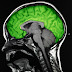

Este sitio fue creado con el propósito de ofrecer información valiosa respecto a las diversas utilidades que presta hoy en día el uso de las radiaciones, tanto ionizantes como no ionizantes, en la salud de la población.